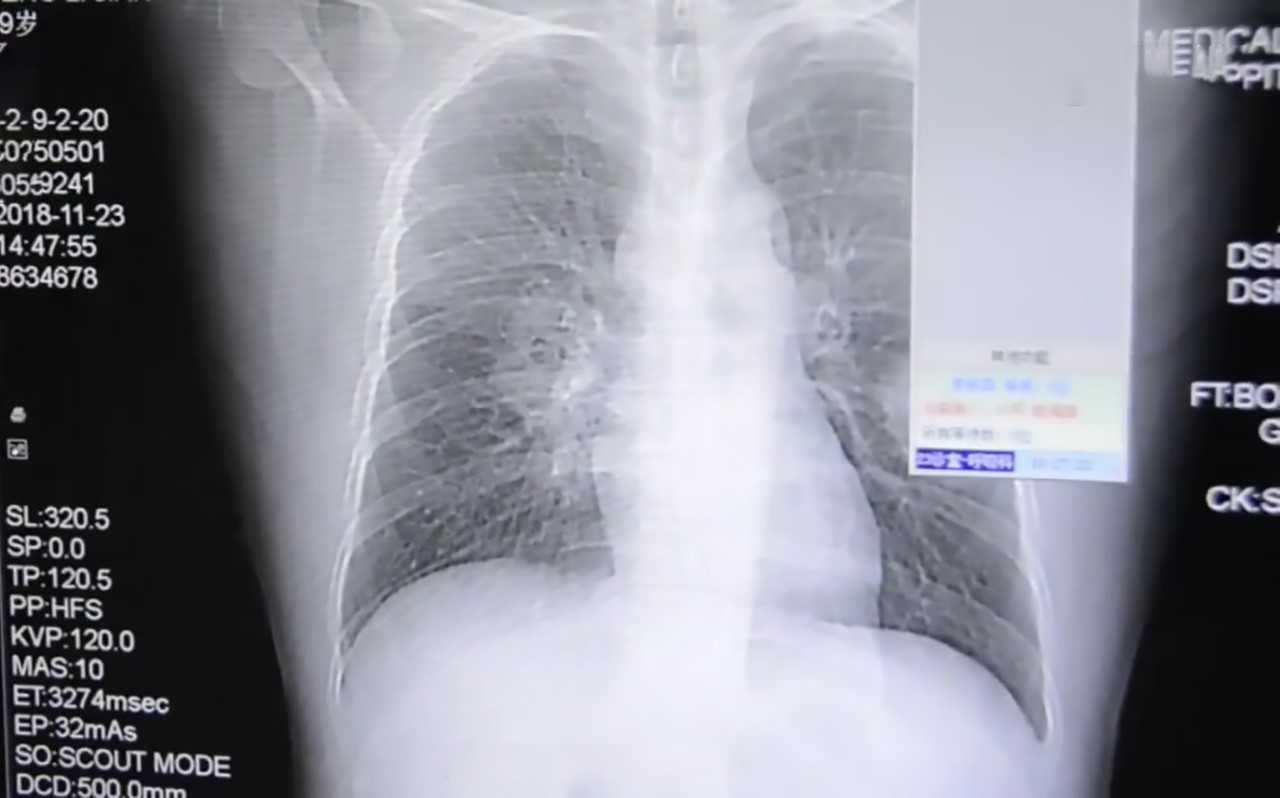

▼醫生見狀為他做了詳細的檢查,經肺部穿刺作檢測,發現他的肺部被真菌侵入。這是怎麼回事呢?在醫生的詢問下,他才表示,自己有一個怪癖,那就是每天下班回家後,都會把臭襪子脫下來聞一聞。他經常熬夜照顧小孩,免疫力下降,再加上壞習慣,這才導致身體不適。

▼醫生表示,患有腳癬的人穿過的鞋、襪很容易滋生真菌。幸好那名男子就醫比較早,並確定了原因,這才逐漸康復。肺部被真菌影響太嚴重,如果沒有及時發現的話,後果非常嚴重。